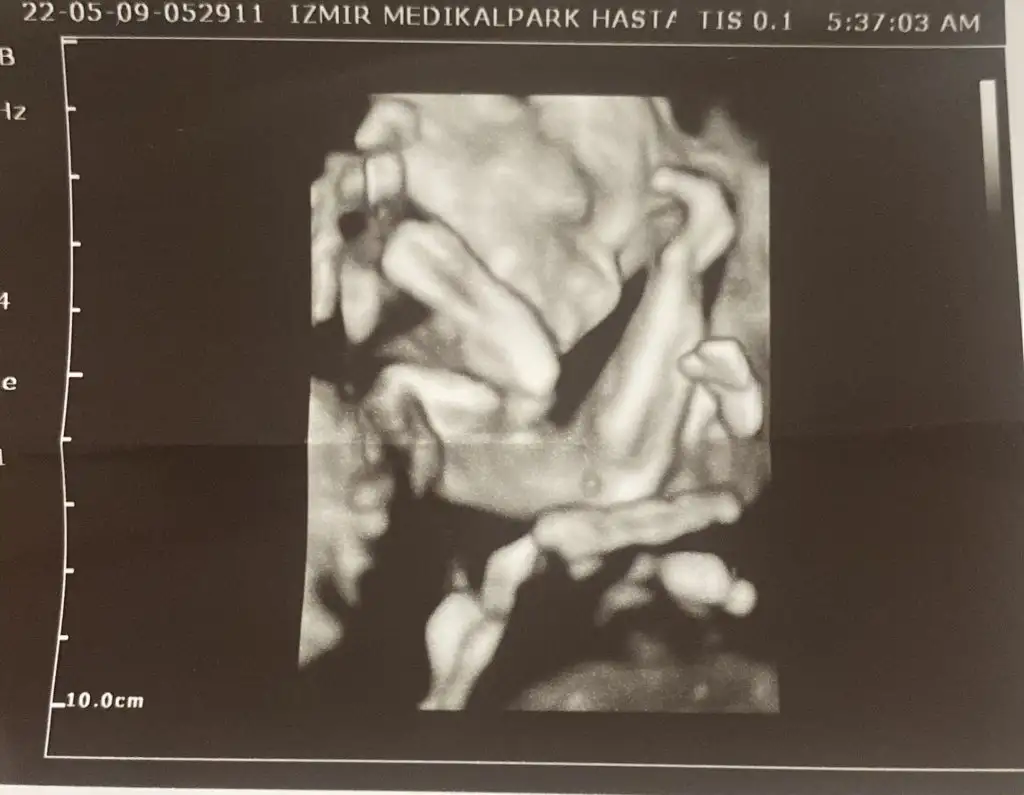

Oyyyt maşallah maşallahBen geldimHer şey yolunda çok şükür kocaman olmuş bebeğim görmeyeli 25cm 401gr 21+0 tam. L Lalalala1

Son olarak güzel bir görüntü bırakıyorum

İnsan bi rahatlıyor görünceOyyyt maşallah maşallah

Gözük aydın canım benim, her şey yolunda kocaman olmuşlar gerçekten, inanılmaz bir hızla büyüyorlar bu aralar zaten.